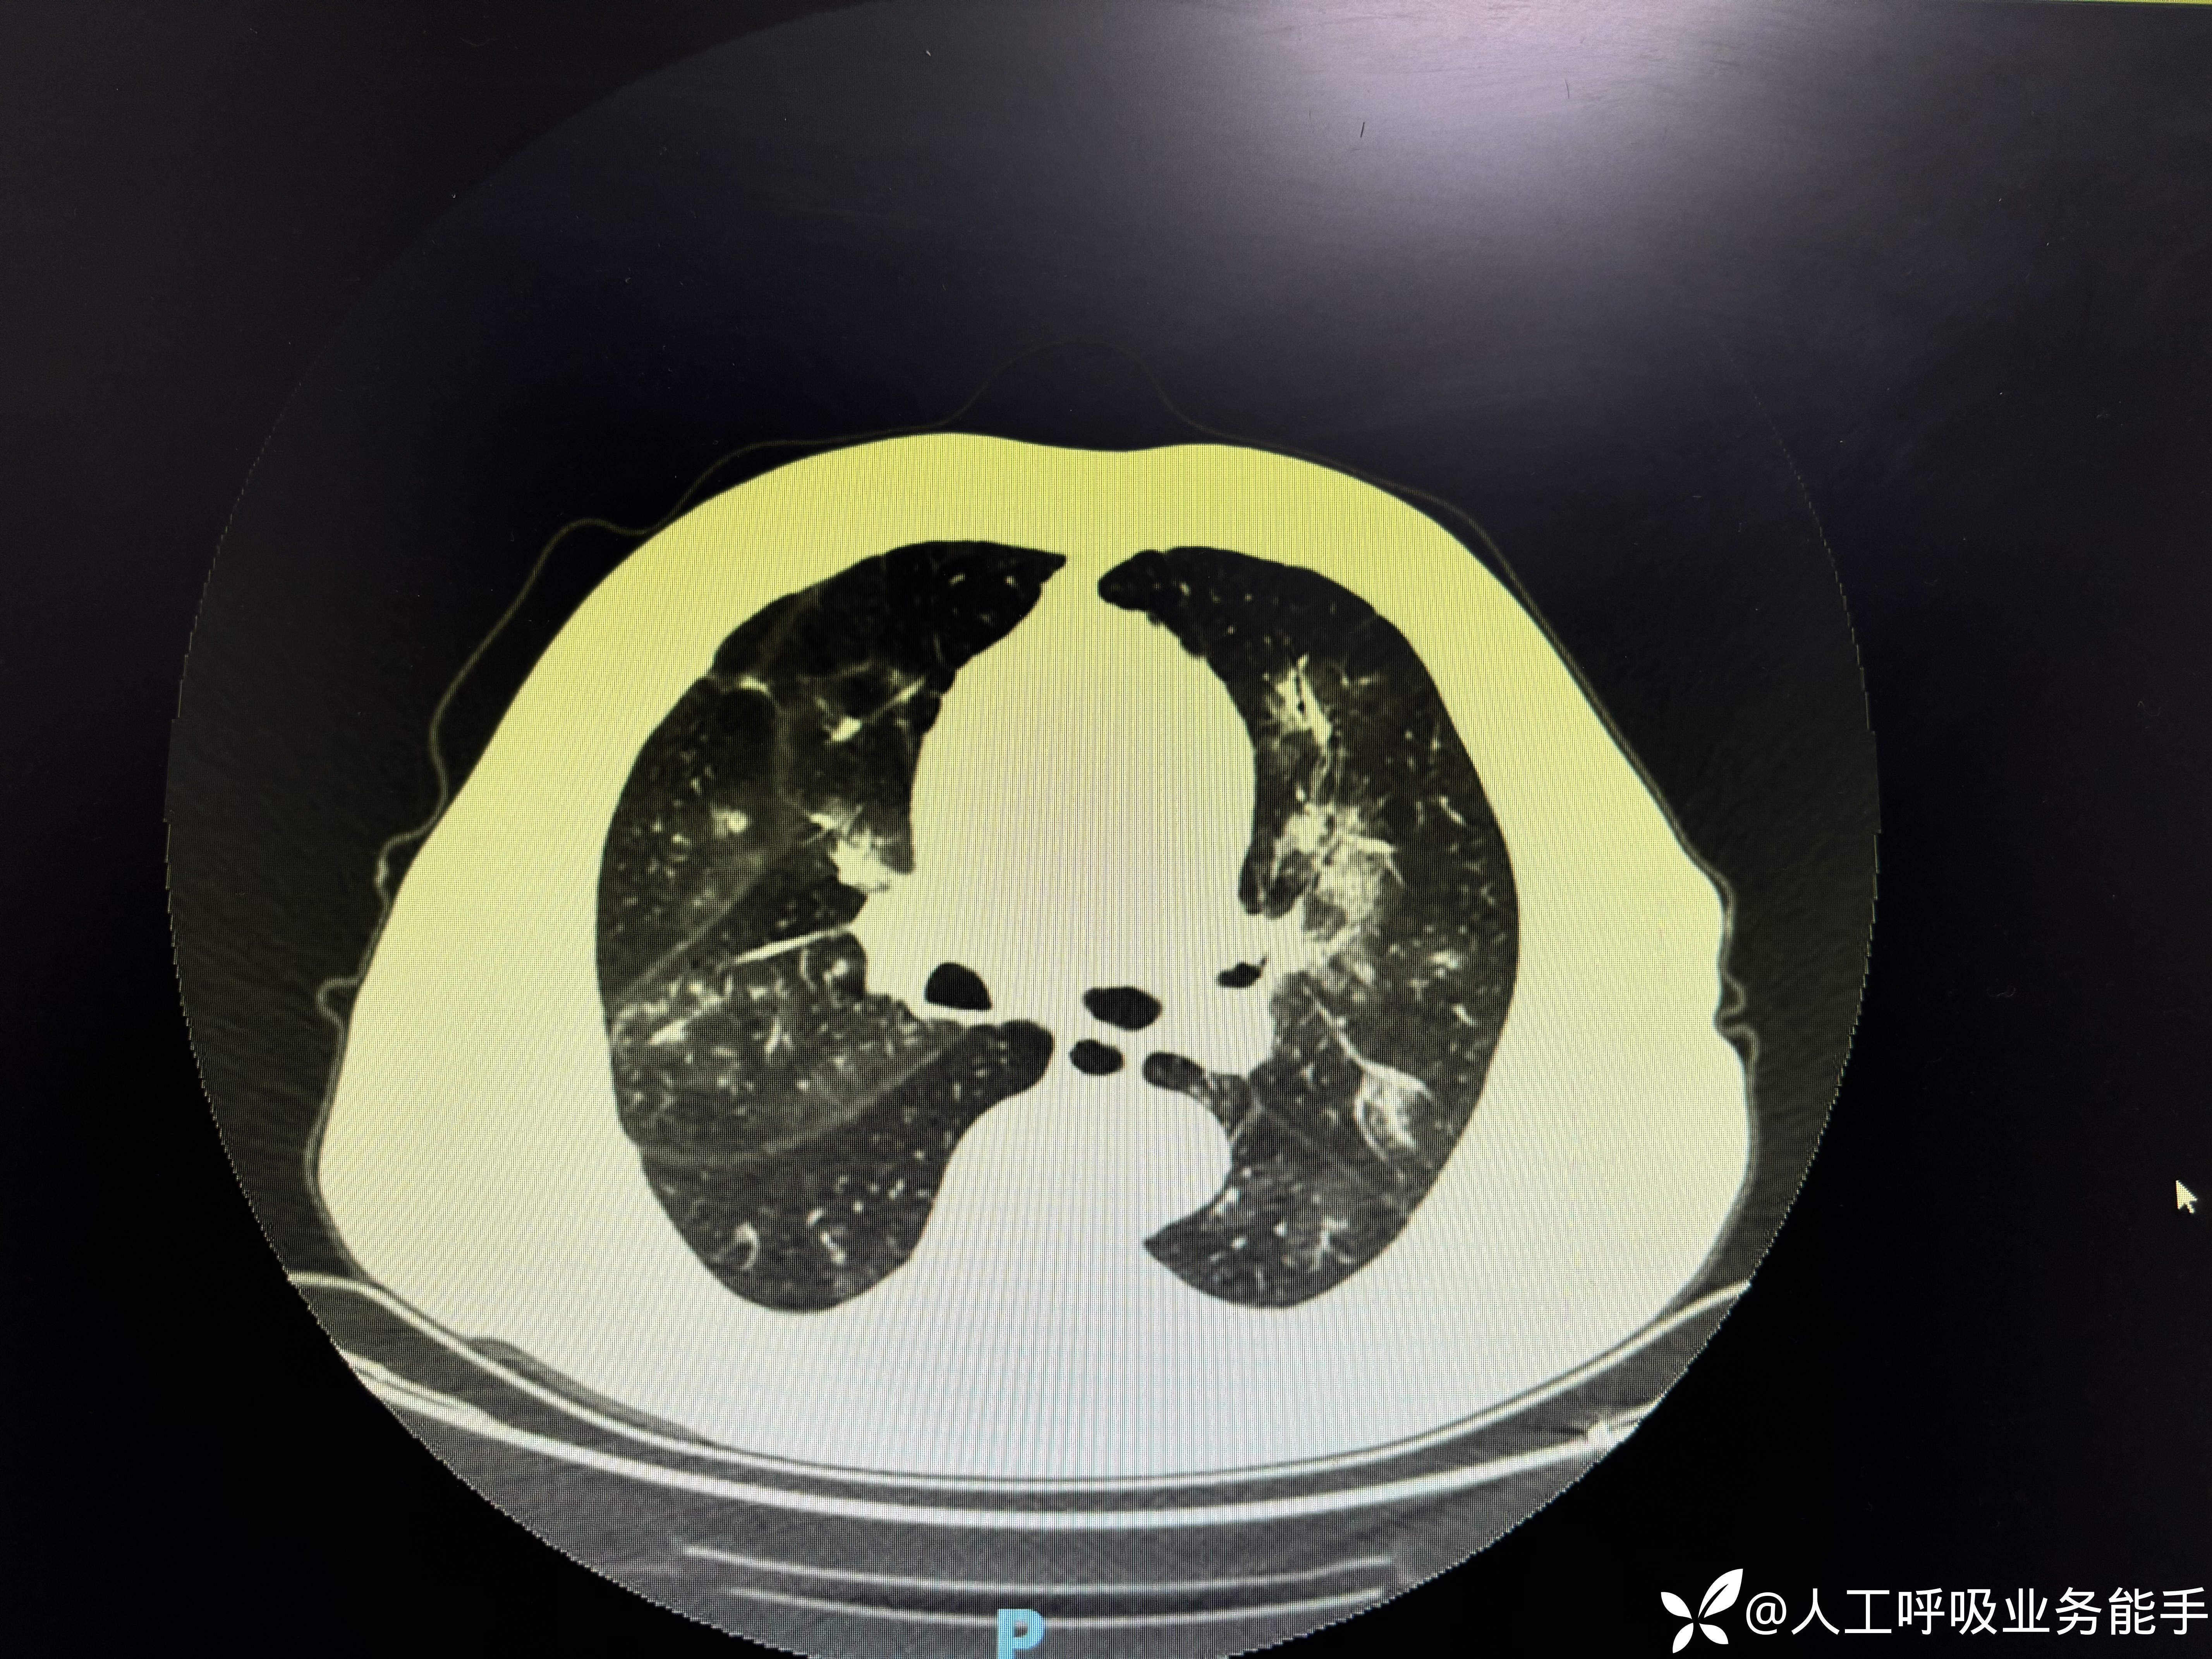

-1/26到我院急诊内科,血常规:WBC 10.71*109/L,CRP 111.6mg/L,Hb 128g/L,PLT 213*109/L,N 68% L 10% Eos 15%;尿常规:黄色清亮,蛋白质 1+,红细胞 2+,白细胞 -,复查胸部CT:

-胸部CT提示双肺多发病变,较前明显进展;